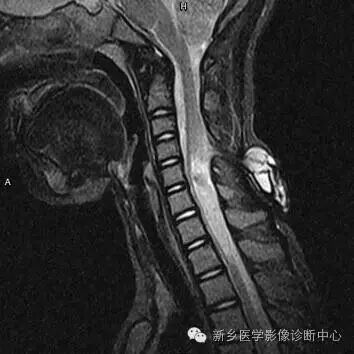

脊柱MRI提示椎管内占位及相应水平椎体后缘扇贝样压迹(白箭)